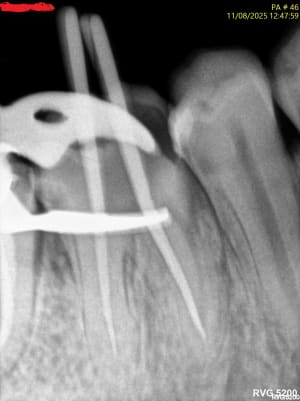

558904719_10163144646272247_6774572045327740986_n.jpg